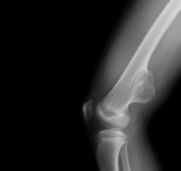

Kemiğin selim-agresif tümörü olarak kabul edilir. Genç erişkinde osteolitik karakterde kemik tümörüdür. Uzun kemiklerin ekleme yakın uç kısmından çıkabilir. Hastalar tümör bölgesinde devamlı ve giderek artan inatçı bir ağrı ve şişlik ile başvururlar.Sadece küretaj yapılan hastalarda yüksek lokal nüks yanında akciğer metastazı yapma potansiyeli olduğundan lokal agresif tümör olarak kabul edilir. Ama bu metastazlar ölümcül değildir.Diz eklemi en sık tutulan bölgedir. Diğer sık tutulan bölge el bileğidir. Kemik korteksini harap ederek yumuşak dokulara yayılım gösterebilir. Tanı için biyopsi şarttır. Brown tümörü ile ayırıcı tanısı yapılmalıdır. Tanı esnasında akciğer tomografisi çekilmelidir.